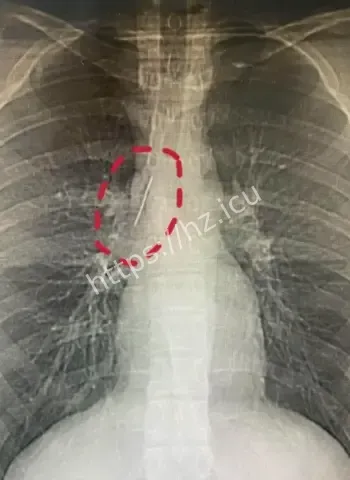

安徽17岁小伙参军体检意外发现胸腔藏5厘米缝衣针,或1岁时扎入后17年安然无恙,奇闻结合医学解读与生活启示,展现人体惊人适应力,引发广泛热议讨论

哎呦喂这事儿听起来就跟天方夜谭一样,一个安徽的17岁小伙子平时活蹦乱跳的,准备去参军体检,结果医生一照X光片子,眼睛直接瞪圆了,胸腔里居然稳稳当当藏着一根5厘米长的缝衣针。这针估计从小时候就钻进去了,整整17年啊,小伙子吃饭睡觉打球跑步啥都没耽误,身体愣是没闹过一点别扭。换成别人早疼得满地打滚了,他倒好,像没事人似的,这运气简直逆天到让人羡慕嫉妒恨。 想想这17年里,针就这么安静待着,没移位没发炎没刺着要害,估计是身体自动给它裹了一层保护膜,把它当成了自家摆设。

最离谱的是,这针很可能他1岁那会儿不小心扎进去的。小宝宝那时候到处乱爬乱抓,说不定妈妈正缝衣服,他一扑腾就中招了,结果针就这么悄无声息地进了胸腔。17年过去,他从奶娃娃长成大小伙,针却一直老老实实待着,没引起任何不舒服。平时感冒发烧都没多想过胸口,这适应力也太强了吧。 从道理上讲,小孩子身体正长着,组织慢慢把针包得严严实实,像给它建了个小房子隔离起来。没碰着肺叶心脏血管,纯靠运气加体质,简直是活生生的人体奇迹。

参军体检意外发现胸腔惊人异物

参军体检本来是查身体合不合格,谁知道成了挖宝现场。X光一扫,医生估计当时就傻眼了,这么大一根针亮闪闪地躺在胸腔里,小伙子自己都蒙圈了,心想我这身体里藏了啥秘密武器啊。幸好发现及时,要不然以后训练强度一大,万一针跑偏了,后果真不敢想。 这事儿也给大伙提了个醒,重要关口体检千万别马虎,尤其是参军这种人生大事,啥隐藏问题都能揪出来。小伙子估计现在又惊又喜,喜的是没出大事,惊的是自己居然带了17年“隐形伴侣”。

医学解读缝衣针与身体和平共处17年

深入扒一扒,这针为啥能跟身体和平共处这么久呢。首先位置挑得好,没扎着要害器官,胸腔空间大给它留了余地。其次人体有自我保护本能,会分泌纤维组织慢慢把它包裹住,防止感染和移位。小时候扎入,身体还在发育,适应起来更容易。再次可能没带细菌进去,运气成分占大头。 这案例搁医学上都算罕见,值得研究研究,说不定以后处理类似异物就有新办法了。不过小伙子以后肯定得做个小手术取出来,不然总是个小隐患。希望手术顺顺利利,他的参军梦还能接着追,这段经历以后说出去绝对是别人听不够的传奇。